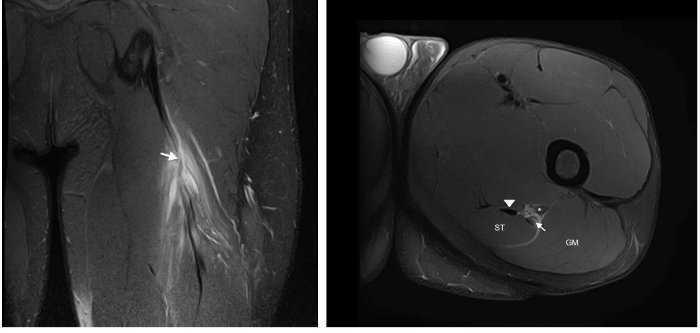

Figura 1 Les imatges coronal i axial en T2 amb supressió de greix de l’isquiotibial esquerre mostren trencament parcial de fibres a la UMT proximal de CLBF representades per una àrea d’alta intensitat de senyal adjacent a la UMT (fletxa). S’observa també ruptura d’algunes fibres del semitendinós (+). Ventre muscular semitendinós (ST), cap proximal del bíceps femoral llarg (long head biceps femoris [LHBF]), tendó semimembranós (punta de fletxa) i nervi ciàtic (*). En el tall coronal s’observa edema muscular de patró de ploma d’au.